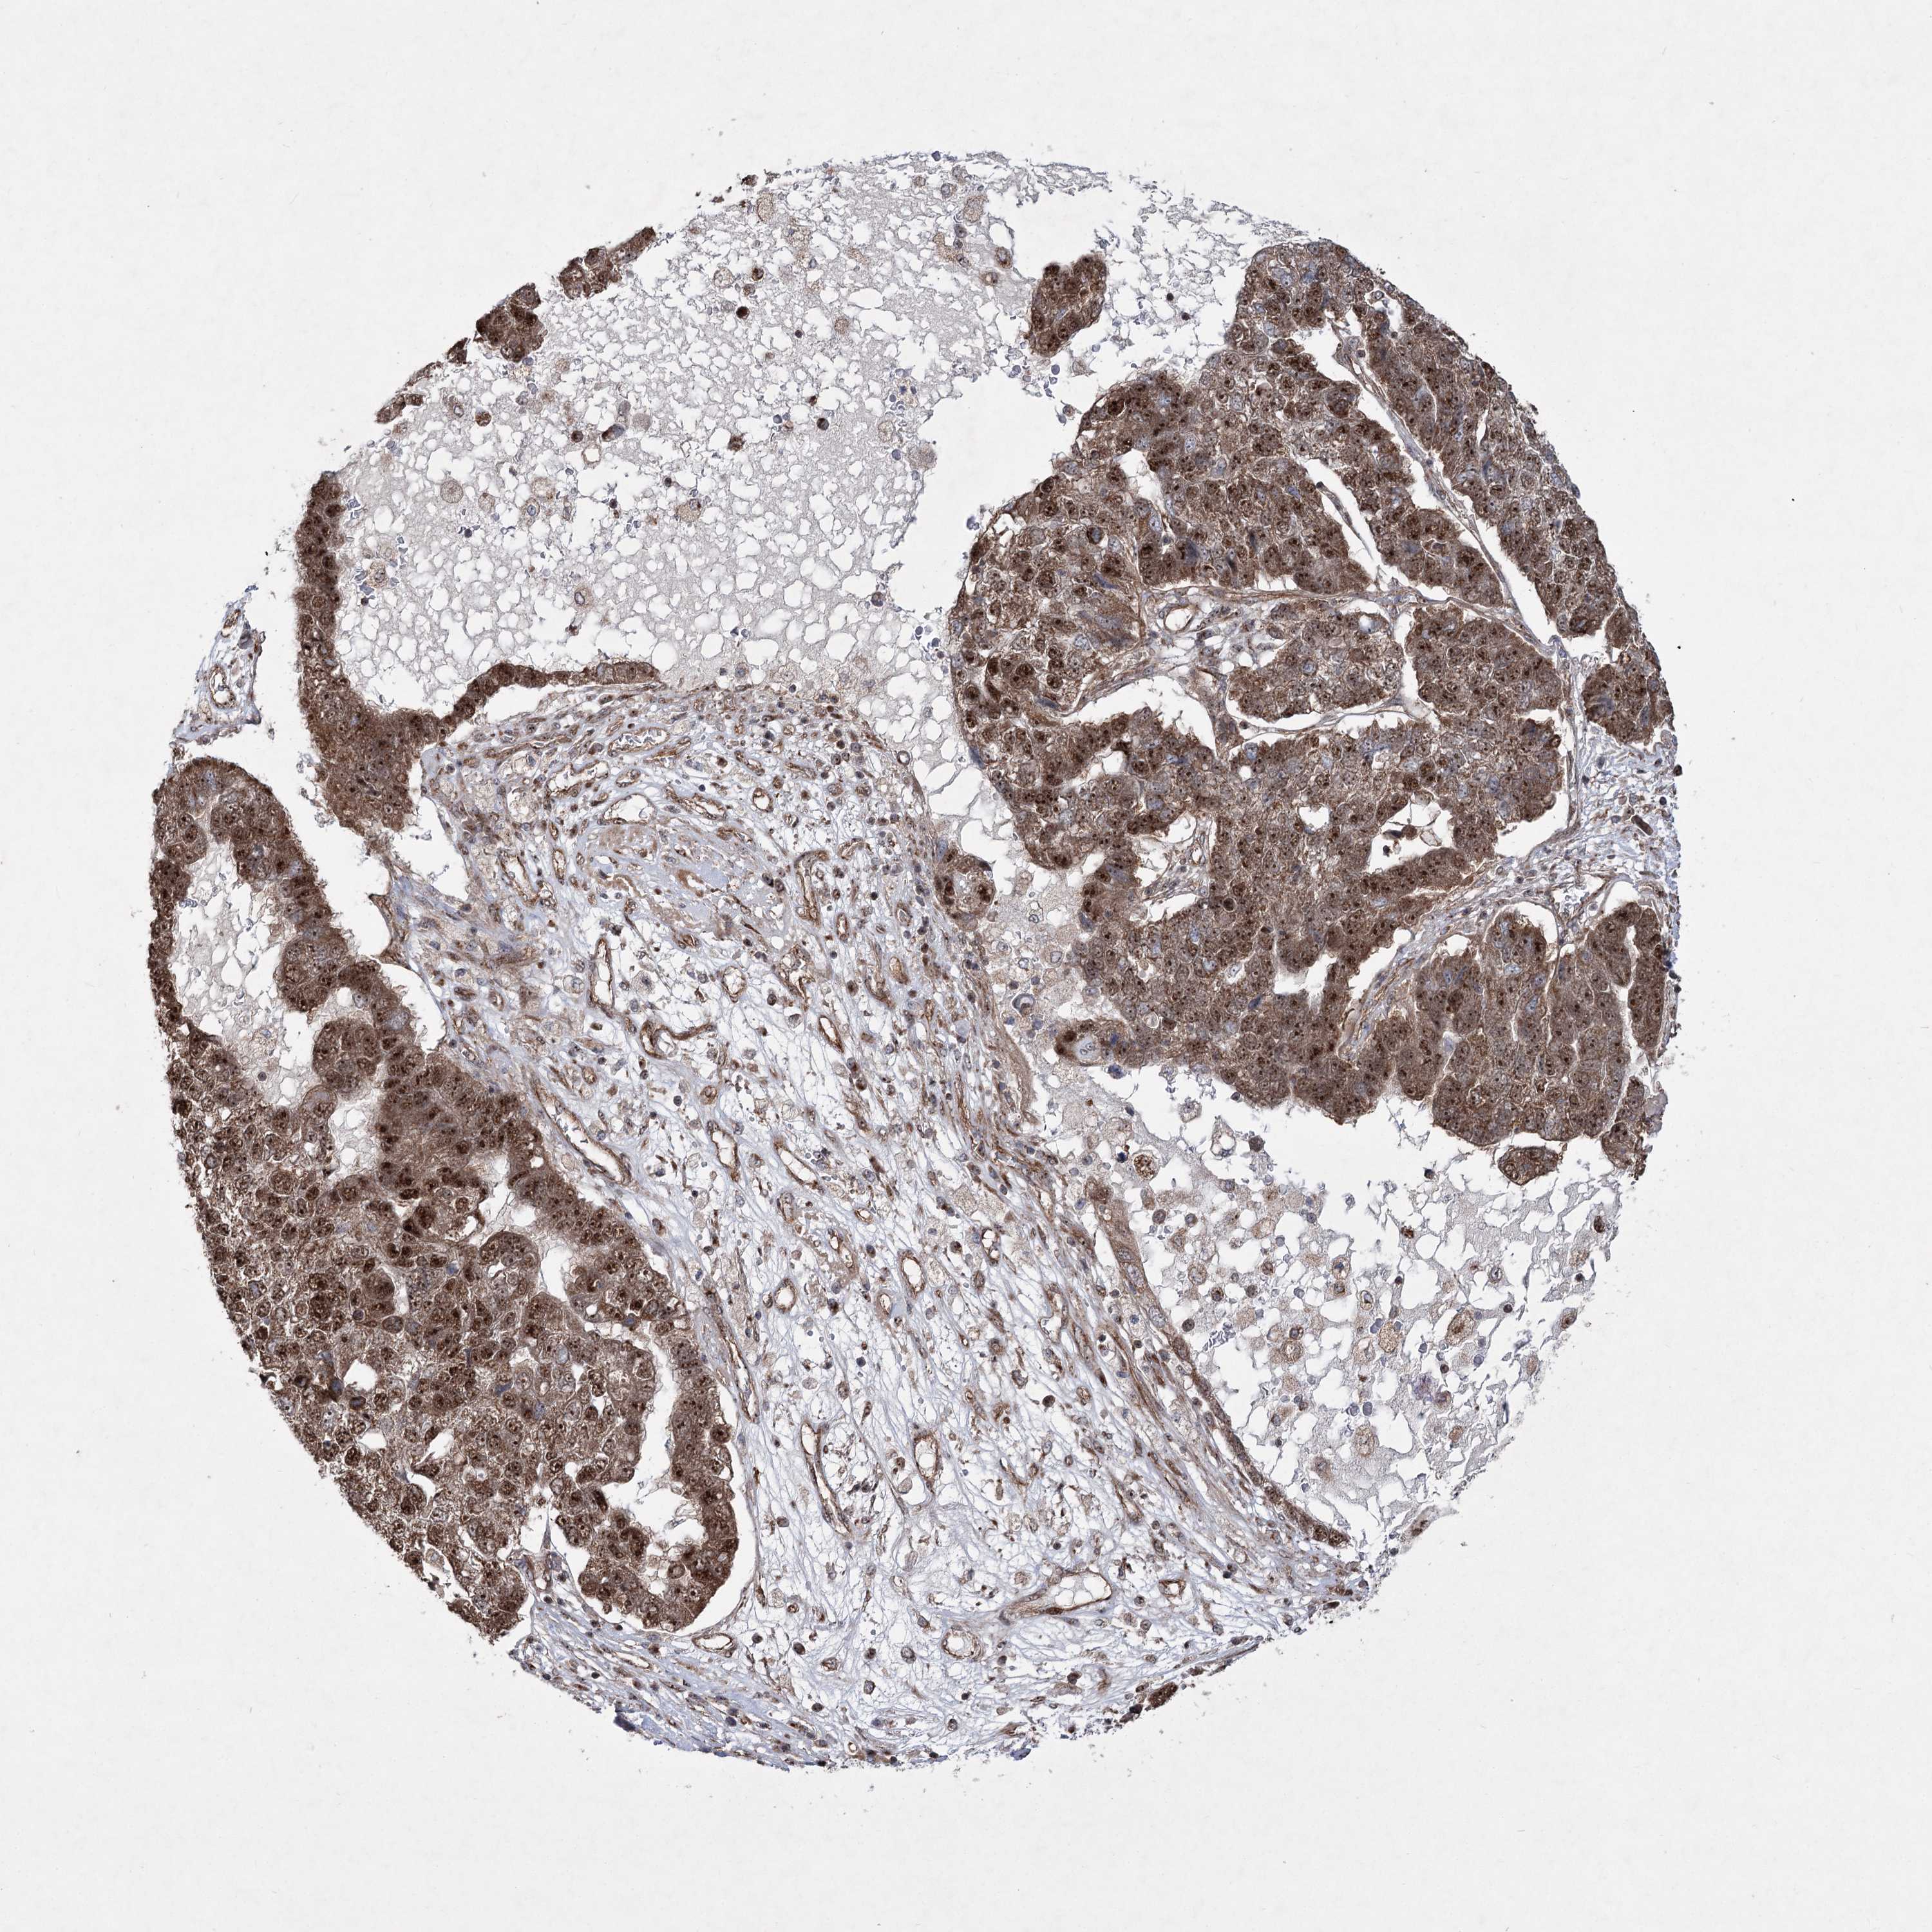

PANCREATIC CANCER - Protein expressioni

A mouse-over function shows sample information and annotation data. Click on an image to view it in a full screen mode. Samples can be filtered based on level of antibody staining by selecting one or several of the following categories: high, medium, low and not detected. The assay and annotation is described here.

Note that samples used for immunohistochemistry by the Human Protein Atlas do not correspond to samples in the TCGA dataset.

Antibody stainingi

Antibody staining in the annotated cell types in the current human tissue is reported as not detected, low, medium, or high, based on conventional immunohistochemistry profiling in selected tissues. This score is based on the combination of the staining intensity and fraction of stained cells.

Each image is clickable and will lead to virtual microscopy that enables deeper exploration of all samples and also displays staining intensity scores, fraction scores and subcellular localization as well as patient and tissue information for each sample.

Antibody HPA037898

Antibody HPA037899

Staining

High

Medium

Low

Not detected

Intensity

Strong

Moderate

Weak

Negative

Quantity

>75%

75%-25%

<25%

None

Location

Nuclear

Cytoplasmic/membranous

Cytoplasmic/membranous,nuclear

Adenocarcinoma, NOS